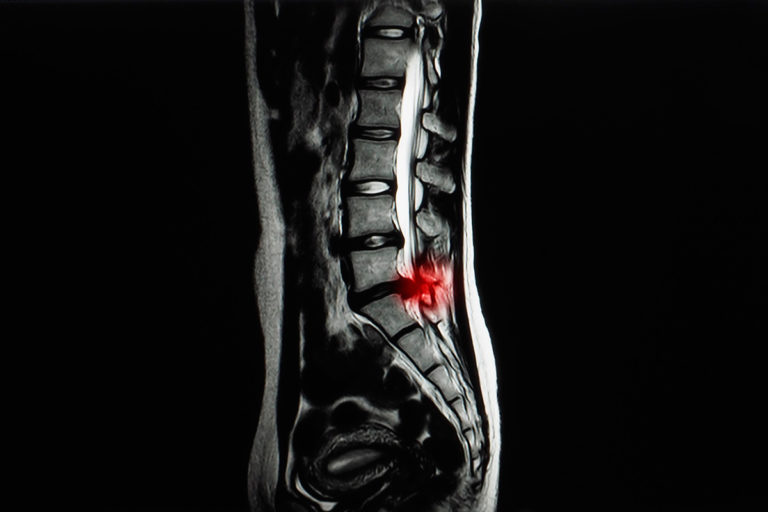

Se trata de una intervención quirúrgica en la que se fijan dos piezas óseas, anclando una articulación. Está indicado cuando hay inestabilidad vertebral.

Procesos tales como espondilolistesis lumbares; escoliosis degenerativas; patología traumática con fracturas y algunos casos de raquiestenosis lumbar.